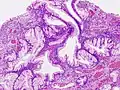

Полип фундальных желёз